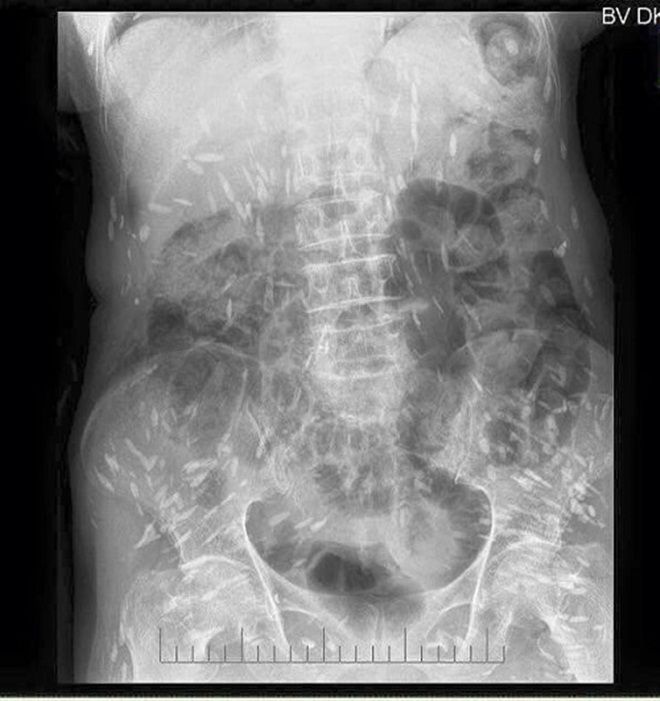

Trong những ngày qua, trên mạng xã hội chia sẻ rất rầm rộ về một hình ảnh chụp Xquang, kèm theo hình ảnh này là lời cảnh báo: “Hình ảnh được ghi nhận tại Bệnh viện đa khoa Trung ương Thái Nguyên.

Người gạo là có thật các bác ạ. Hình ảnh XQ trên là của bệnh nhân nhiễm sán xơ mít do ăn phải thức ăn sống (có thể là rau sống, tiết canh, gỏi cá…) có nhiễm trứng, ấu trùng sán…”.

Rất nhiều người khi quan sát hình ảnh này không khỏi hốt hoảng khi hình những nốt trắng được cho là sán sơ mít có ở khắp cơ thể. Thậm chí, có người còn bình luận: “Người nhiều sán thế này, có khi đứt tay máu không chảy mà sán lại chạy ra”.

Có nguồn tin cho rằng, đây là hình ảnh phim của bệnh nhân Nguyễn Thị Th. (69 tuổi) trú tại Đồng Hỷ - Thái Nguyên nhiễm sán dây, bệnh nhân Th., nhập viện viện Trung ương Thái Nguyên ngày 26/09/2016.

Để có thông tin rõ hơn về mặt chuyên môn, chúng tôi đã chuyển hình ảnh này đến BS Trần Huy Thọ - Trưởng khoa Điều trị (Viện Sốt rét - Ký sinh trùng - Côn trùng Trung ương), thì được biết, viện cũng đã gặp nhiều trường hợp bị sán cơ, tuy nhiên nhìn hình ảnh như trên phim thì bản thân bác sĩ Thọ chưa gặp bao giờ.

“Nhiều khả năng đây là sán cơ, tuy nhiên để khẳng định chính xác thì tôi phải hỏi bệnh sử, có hồ sơ bệnh án, kết quả làm các xét nghiệm, thậm chí là cả địa phương nơi đó tập quán ăn uống như thế nào, nếu chỉ nhìn vào hình ảnh thì không thể khẳng định 100%”, BS Thọ cho hay.

Theo bác sĩ Thọ, trong trường hợp sán cơ nhiều như vậy, thì đó có thể là những nốt vôi hóa ở trong cơ. “Đây có thể là những nốt vôi hoá trong cơ, khi nang sán trong cơ thoái triển và thành vôi hoá”, BS Thọ cho biết.